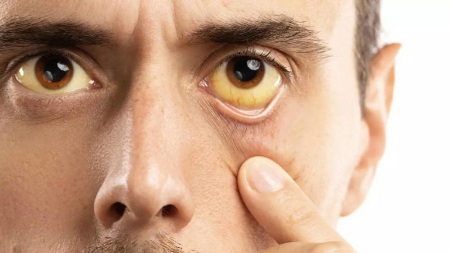

۷٫ زرد شدن سفیدی چشم – ارتباط با زردی (جانديس)

آیا تا به حال متوجه زردی سفیدی چشمهایتان شدهاید؟ به این حالت زردی یا «جانديس» میگویند و یکی از واضحترین نشانههای مشکل کبدی است. زردی وقتی رخ میدهد که بیلیروبین (مادهٔ زردرنگی که از تجزیهٔ گلبولهای قرمز خون به وجود میآید) در خون زیاد شود. کبد سالم بیلیروبین را سریعاً دفع میکند، اما کبد آسیبدیده این کار را نمیتواند انجام دهد و در نتیجه چشمها زرد میشوند. این علامت را جدی بگیرید! زردی میتواند نشانهٔ آسیب کبدی، سیروز یا بیماریهای کبدی باشد. اگر این نشانه را دیدید حتماً با پزشک مشورت کنید.